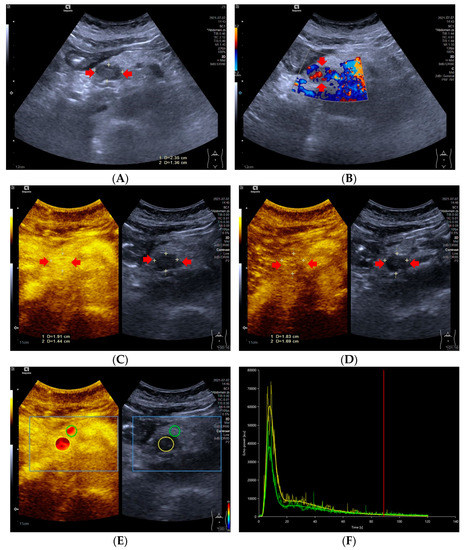

Figure 1.

A 59-year-old female with a pNETs G1 lesion (Ki 67 proliferation index of 2%). The pNETs lesion located in pancreatic head was hypoechoic (A) with abundant internal color doppler flow imaging signal (B). After injecting the contrast agent, pNETs lesion showed hyperenhancement in the arterial phase (C) and isoenhancement in the venous phase (D). The pNET’s microvascularization was assessed using VueBox®, an external perfusion software. Regions of interest of the pNETs lesion (yellow circle) and surrounding pancreatic parenchyma (green circle) were placed manually (E). The time intensity curve revealed that in the arterial phase, the yellow curve (pNETs lesion) was higher than the green curve (pancreatic parenchyma), and in the venous phase and late phase, the two curves almost completely overlapped (F).